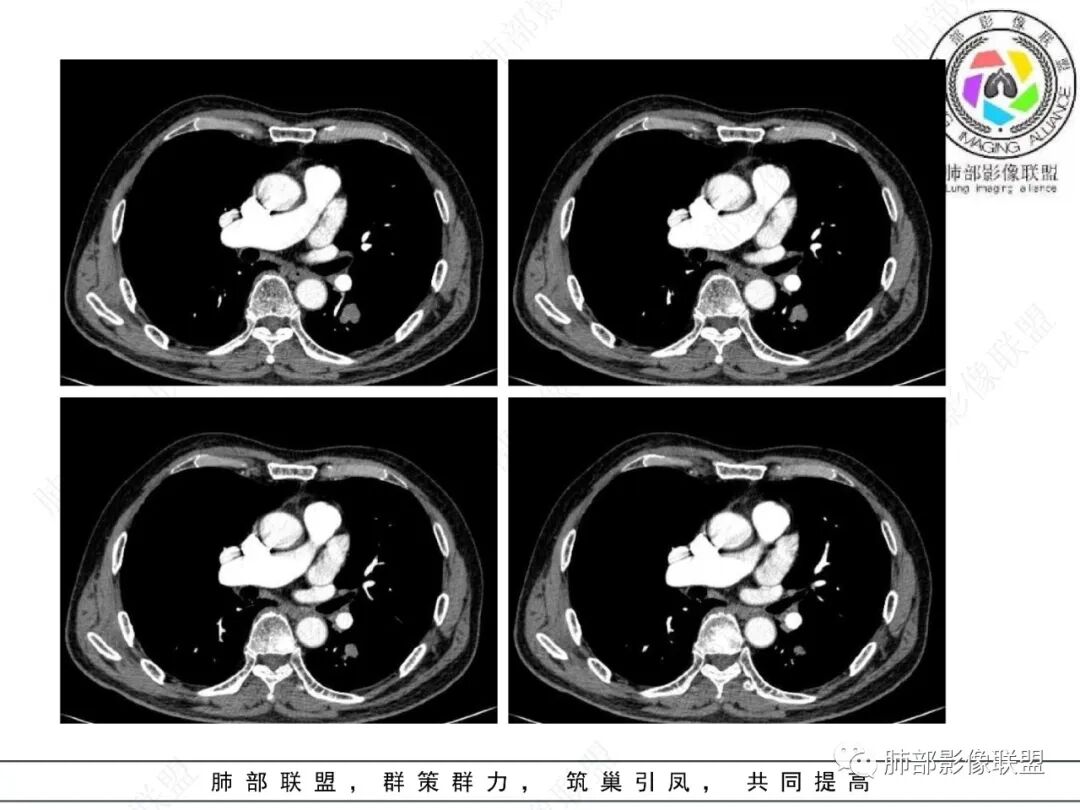

影像学表现:左肺下叶背段近叶间裂旁不规则实性密度结节影,图像未明确显示与支气管关系。边界清,整体膨隆感较明显,边缘显示分叶,偶见段毛刺,叶间胸膜“L”形牵拉凹陷,密度均匀,未见空洞或液化,也未见明显脂肪密度及钙化,轻到中度渐进性强化,未见明确蛇纹状血管应。左肺门可见多发小淋巴结影,纵隔内未见明显肿大淋巴结影。

未见明确卫星灶。